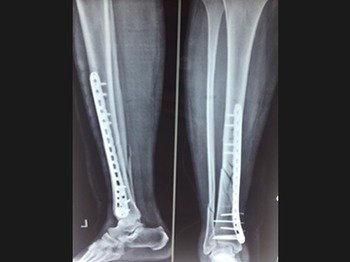

Dr. M.S. Narula is a leading trauma orthopaedic surgeon who offers minimally invasive and small incision techniques to provide state of the art care to his patients. Whether you require a second opinion or emergency treatment, he offers specialized fracture management for simple, complex and neglected fracture.

Orthopedic trauma cases are particularly difficult to treat, but with the right skill, technique, and experience, Dr. M.S. Narula provides excellent care to treat the trauma and progress towards complete recovery & minimal or no disability.

These surgeries are the most difficult and challenging to treat. Dr Narula uses 3 generation techniques with special implants and Grafts to treat such complicated cases.